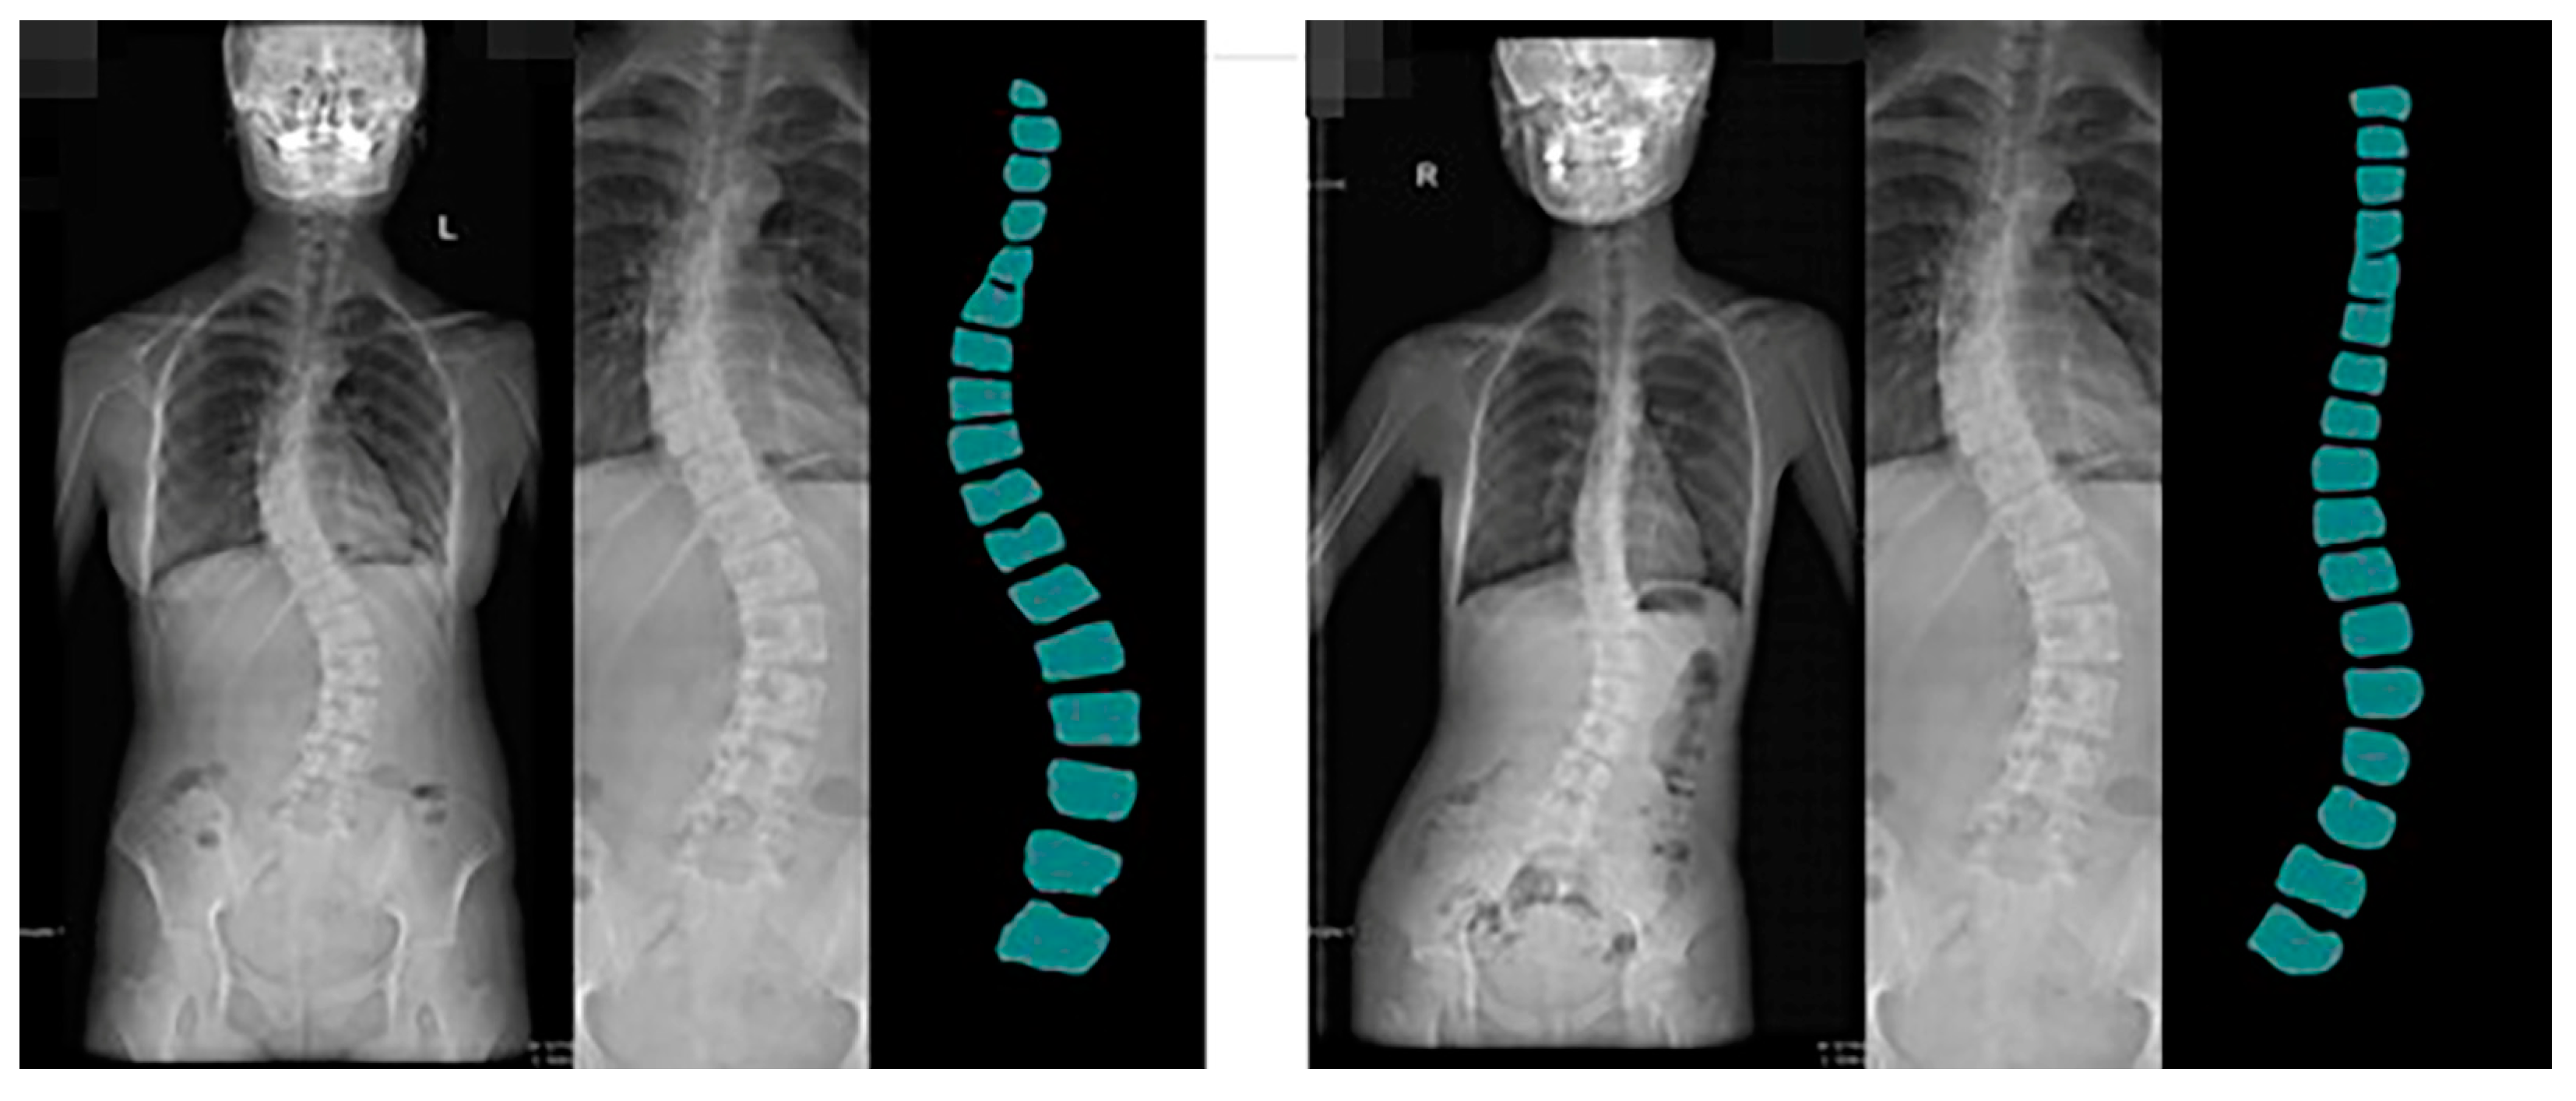

Guizhou Province is the most affected area by coal-fired fluorosis. The coal-burning type of ground fluorosis, and coal-burning polluted endemic fluorosis is a type of ground fluorosis unique to China in the world, affecting about 15 million people, with about 10 million people suffering from dental fluorosis and about 1 million people suffering from bone fluorosis. Fluorosis severely affects residents’ bone health and quality of life [54]. The spine dataset of the Guizhou branch of Beijing Jishuitan Hospital uses X-ray images of the spine medical images, which reflect the bone quality of the inhabitants of Guizhou province, China, between the ages of 18 and 70. Due to geological conditions and the level of economic development, middle-aged and elderly residents have poor height development and often suffer from a range of diseases, including scoliosis, which is particularly serious. This dataset was developed in collaboration with the Guizhou branch of Beijing Jishuitan Hospital. Many ortho X-ray medical images of residents in Guizhou province were retrieved to produce the dataset. Due to privacy and legal issues, this dataset cannot be made public, and this dataset is labeled by is manually labeled. The segmentation prediction results generated by CI-UNet are shown in Figure 16.

Figure 16. The segmentation prediction results generated by CI-UNet.